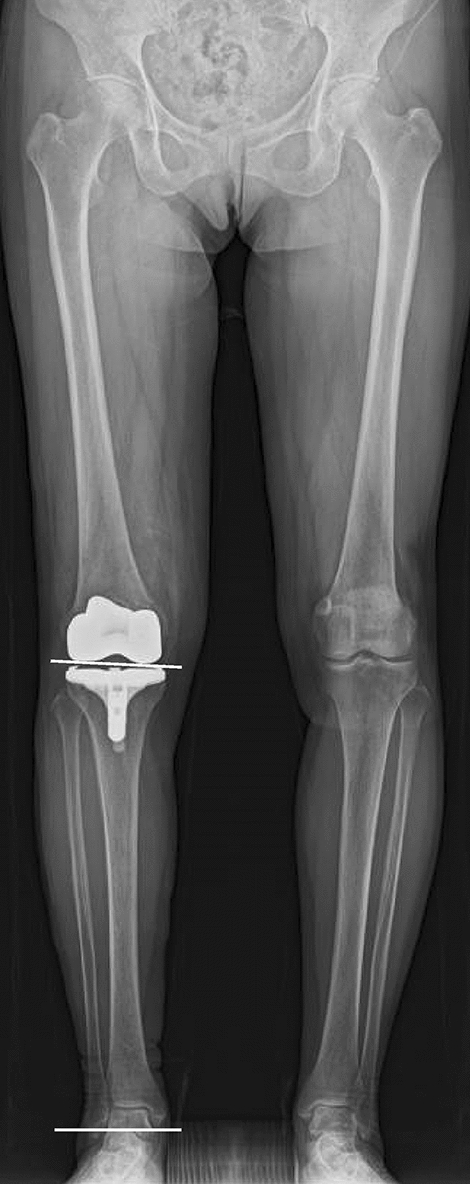

This study included 145 primary TKAs in 145 patients with osteoarthritis (OA) who received a cruciate-retaining type of the FINE total knee (Teijin-Nakashima Medical Co. Ltd., Okayama, Japan) (Fig. 1) at our hospital between February 2015 and February 2019. Exclusion criteria were patients with an impaired posterior cruciate ligament, bilateral TKAs, valgus knees < 170° of the femorotibial angle (FTA), flexion contracture of 30o or more, deformed femur or tibia following trauma, or dementia at the time of recording clinical scores.

Figure 1.

The FINE total knee. The femoral condyle has an asymmetric shape and femorotibial joint line with an inclination of 3° both in coronal (left) and axial (right) planes. The medial and lateral condyle have different length of radii (medial larger than lateral), resulting in medially inclined joint line both in extension and flexion. The medial surface of the polyethylene insert has a convex curve while the lateral surface has a flat surface. The figure is reprinted with minor modifications from Fig. 1 in reference 13.